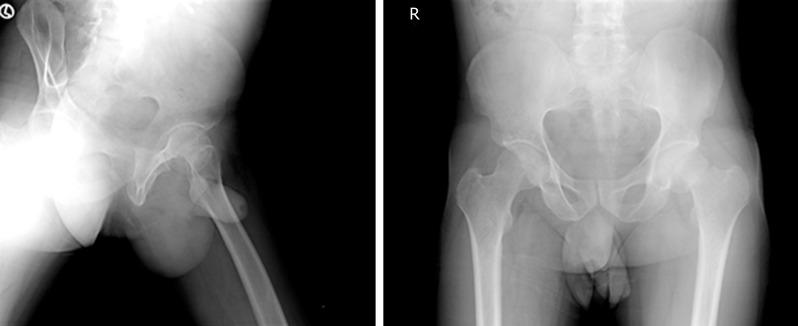

A 35-year-old HIV positive male presented with a stress fracture of left femoral neck. The patient was on ART and reported no comorbidities. He went on to be successfully managed surgically. However, during work-up osteopenia of the contralateral proximal femur was recognised using Singh's Index. Six months post-op the patient presented with right-sided femoral - neck stress fracture. At this stage the patient was nonconcordant with ART and denied surgical fixation.

In the absence of co-morbidities, several mechanisms of HIV/antiretroviral therapy may have played a role in predisposing our patient towards such a presentation. We recommend routine screening all HIV-infected patients for osteopenia, especially in younger individuals. In low resource settings and district hospitals, pelvis radiograph & Singh's index can be used for screening.

一名35岁的HIV阳性男性因左股骨颈应力性骨折就诊。该患者正在接受ART治疗,且无合并症。他接受了手术治疗并成功康复。然而,在检查过程中,通过辛格指数发现对侧近端股骨存在骨质减少。术后六个月,患者出现右侧股骨颈应力性骨折。此时,患者未坚持ART治疗且拒绝手术固定。

在无合并症的情况下,HIV/抗逆转录病毒疗法的多种机制可能促使我们的患者出现这种情况。我们建议对所有HIV感染患者进行常规骨质减少筛查,尤其是年轻患者。在资源匮乏地区和地区医院,骨盆X线片和辛格指数可用于筛查。